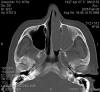

JFC Sinusitis maxilar. Espolón septal.